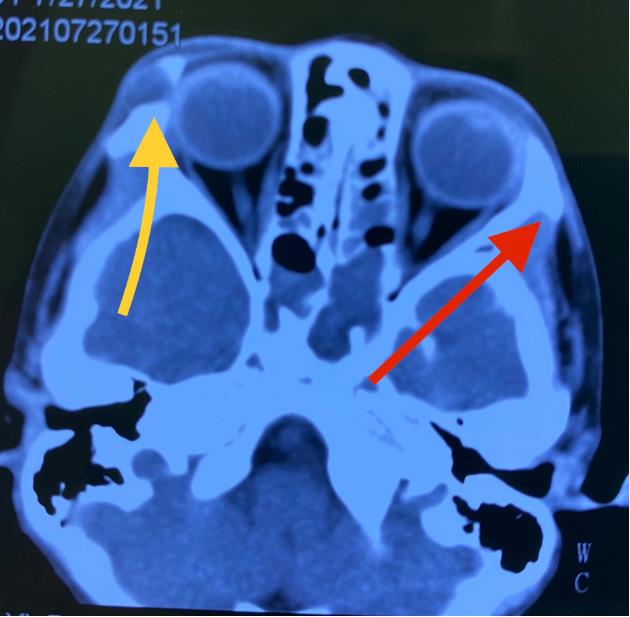

眉弓锁孔入路夹闭前交通动脉瘤新乡市中心医院邢振义